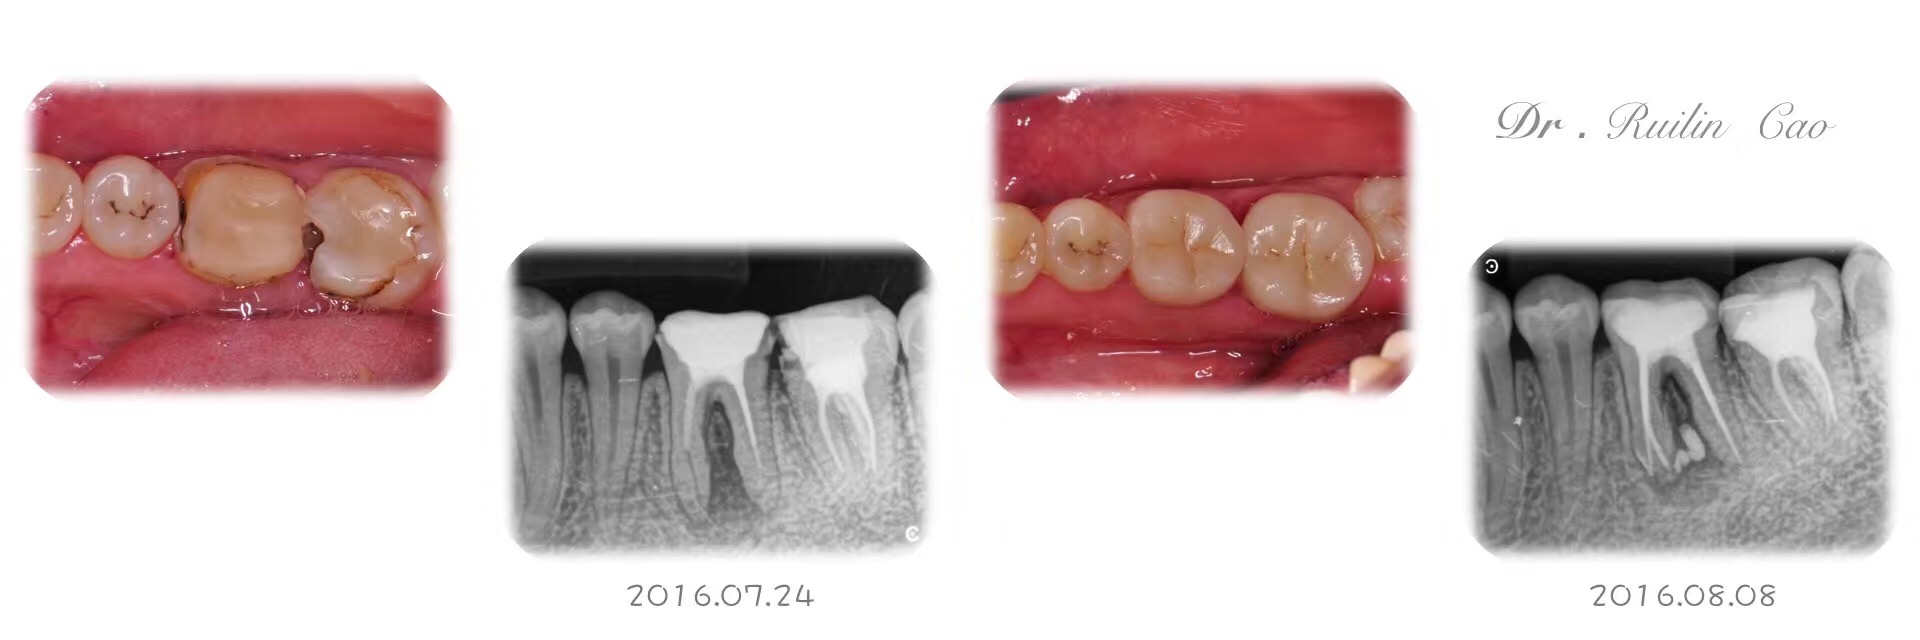

嵌体|E-Max .36.37

Published on Aug 9, 2016

泽国呈祥口腔 曹瑞麟 医生 | 技师:尹群